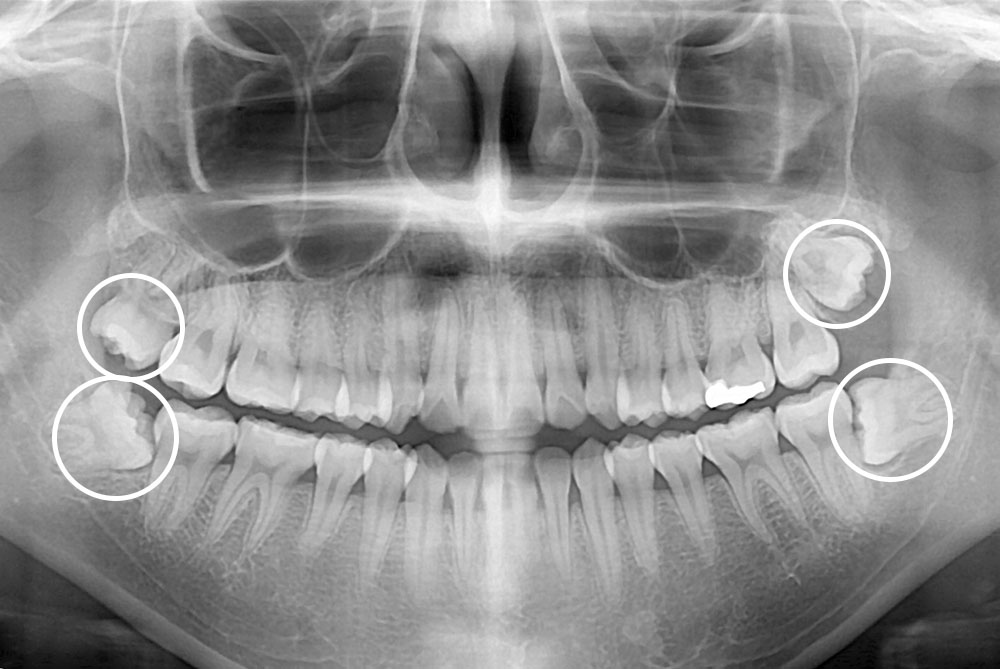

[사랑니] 매복 사랑니 발치

치료후 : 2019-12-30

세종치과는 구강악안면외과학 박사이신 원장님이 발치하는 치과입니다.